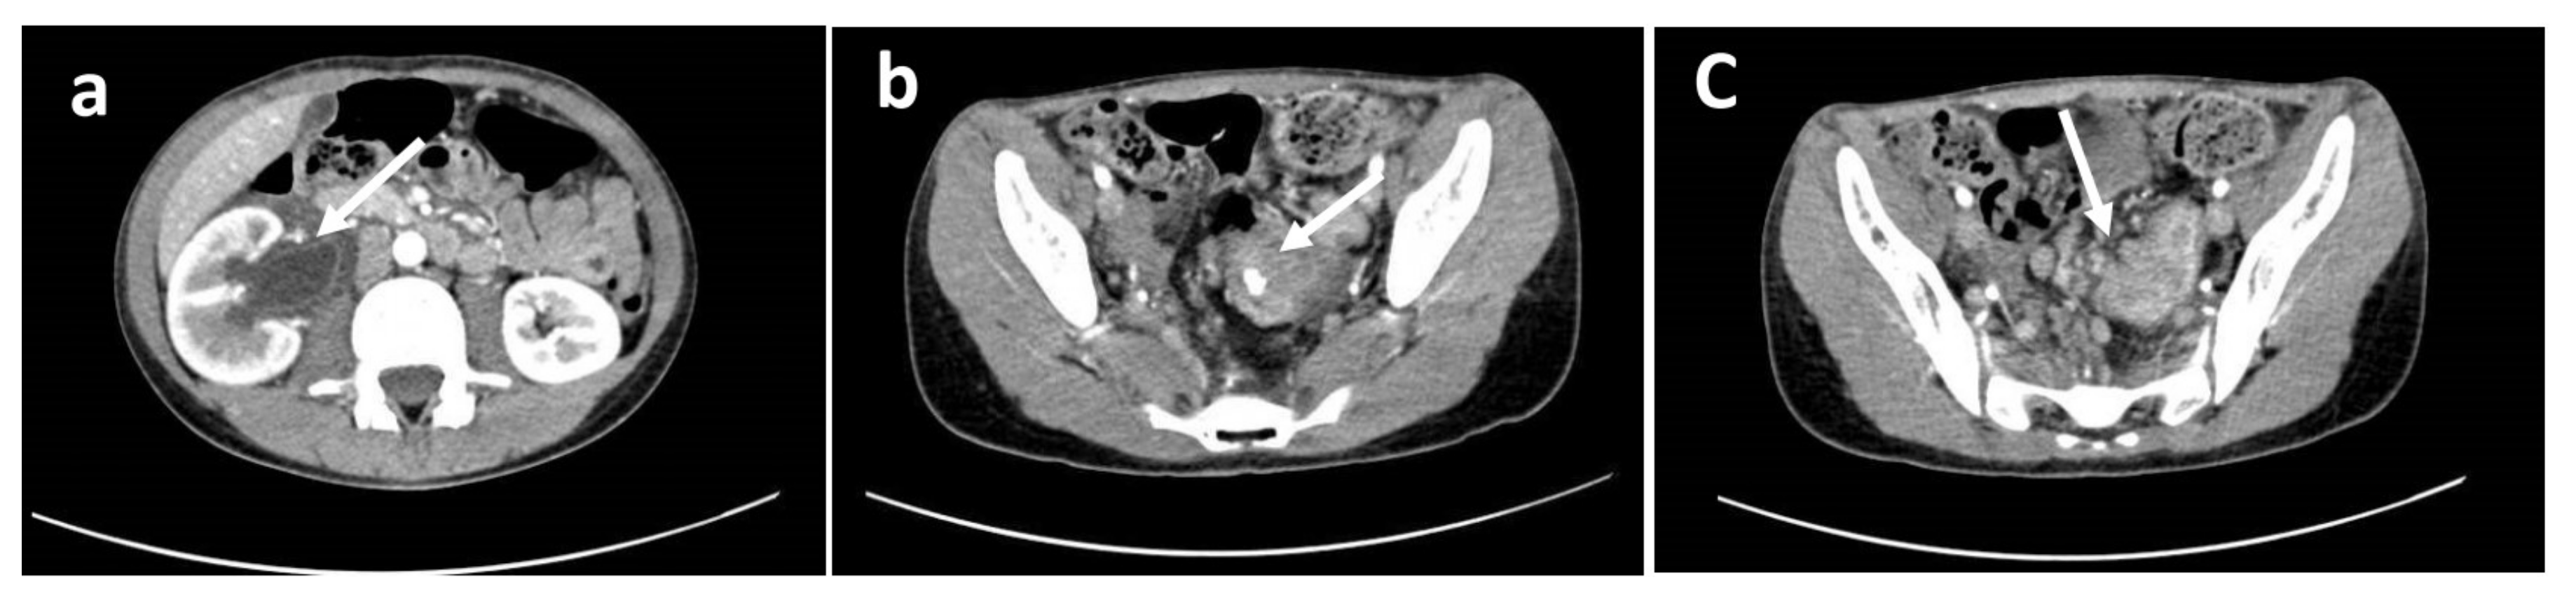

After an open biopsy of the nodal mass, the pathology revealed lymph-node metastasis from epithelial neoplasia, while the analysis of the peritoneal fluid, collected during surgery, revealed the presence of neoplastic cells. Colonoscopy revealed a large polypoid mass of the sigmoid colon, measuring about 5–7 cm in diameter and lying about 20 cm from the anal verge. The lesion almost completely occluded the colonic lumen, allowing a small endoscope (diameter 4.9 mm) to pass, albeit with some difficulty (Figure 2). Multiple biopsies were performed, with the pathology revealing undifferentiated adenocarcinoma (Figure 3). An evaluation of tumor markers showed a high level of carbohydrate antigen (CA) 19-9, 330 UI/mL (normal value < 37 UI/mL) while carcinoembryonic antigen (CEA) levels were normal.

Figure 2. Colonoscopy image showing the large polypoid mass of the sigmoid colon (about 20 cm from the anal verge) that almost completely occluded the colonic lumen.